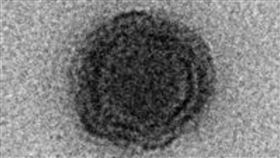

巴西驚現神祕病毒 90%基因沒紀錄

新型冠狀病毒肆虐全球,沒想到有科學家卻在巴西人造湖「...